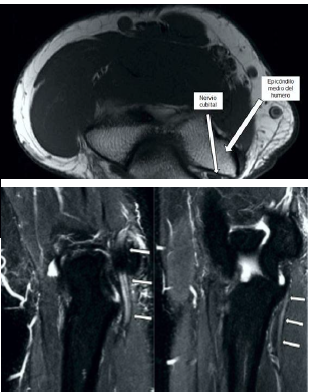

La electromiografía mostró evidencia de compresión en el surco cubital con reducción de la conducción motora cubital en el codo, sin evidencia de denervación en los músculos, sugiriendo la posibilidad de neuropatía cubital del codo izquierdo. La extremidad superior contralateral no demostró alteraciones. Las imágenes de resonancia magnética del miembro superior izquierdo demostraron presencia del músculo ancóneo epitroclear con ligero engrosamiento y señal hiperintensa del nervio cubital en el sitio de compresión por el músculo (figura 1 y 2). La evaluación clínica, neurofisiológica y de imágenes llevó al diagnóstico de neuropatía cubital del codo causada por atrapamiento del nervio cubital por músculo ancóneo epitroclear.

No obstante, las pruebas neurofisiológicas no proporcionan información anatómica o morfológica sobre el túnel cubital o el nervio cubital. El músculo ancóneo epitroclear puede identificarse por ultrasonido de alta resolución o en imágenes de resonancia magnética, las cuales son modalidades confiables para mostrar anomalías estructurales e identifican la causa de la neuropatía cubital, así como las variantes anatómicas. La ecografía puede distinguir nervios de músculos y tendones por su textura diferente y su relativa movilidad durante las maniobras de flexión-extensión (11). En la resonancia magnética el músculo ancóneo epitroclear es visible en cortes axiales, donde las relaciones con el nervio cubital y estructuras vecinas están mejor delimitadas. El edema en este músculo se puede detectar en imágenes ponderadas en T1(12).